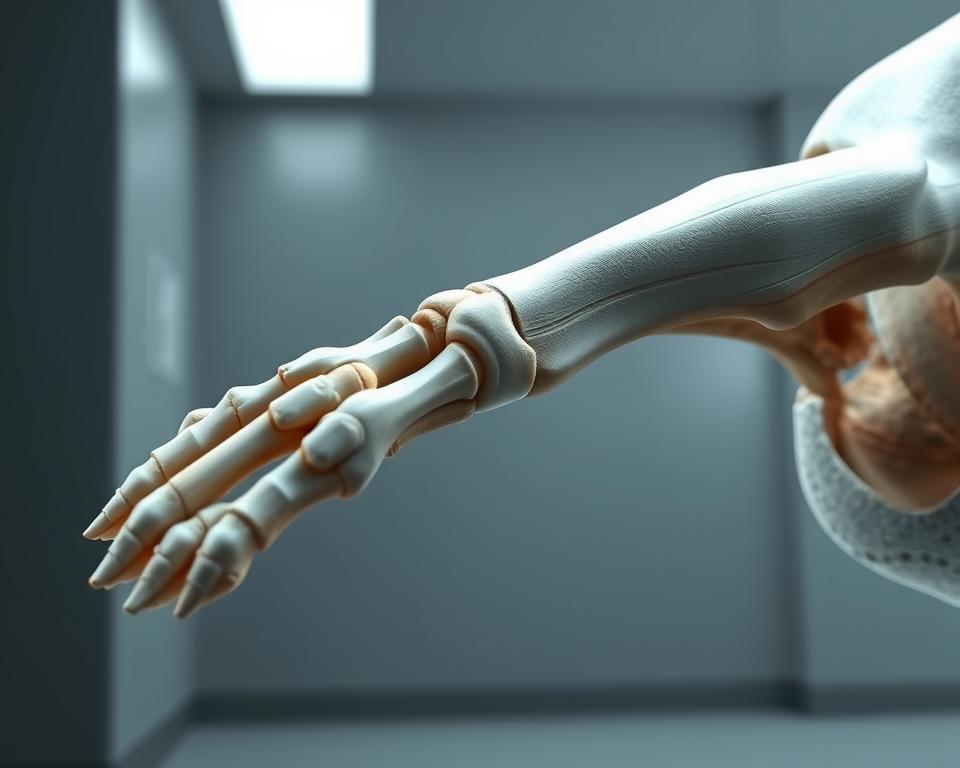

Osnovno poznavanje zgradbe kosti pomaga razumeti, zakaj se nekateri zlomi teže zacelijo. Proces celjenja je kompleksen in poteka v več fazah. Vsaka faza igra pomembno vlogo pri obnovi poškodovane kosti.

Kostno celjenje pri psih sledi štirim ključnim fazam. Začne se z vnetno fazo, ki traja od 1 do 7 dni. V tej fazi se tvori hematom in aktivirajo mediatorji, ki podpirajo popravilo kosti. Sledi faza nastanka mehkega in trdega kalusa, kar zagotavlja umiritev zlomljenih delov in njihovo postopno mineralizacijo. Celjenje je pri mladih psih hitrejše, vendar zahteva skrbno nadzorovanje obremenitve.

V obdobju mehkega kalusa, ki traja od 1 do 3 tedne, je ključna stabilnost in kontrolirano gibanje. Med 3 in 8 tedni, v fazi trdega kalusa, osteoblasti kost obnovijo z minerali. Ta postopek zahteva skrbno nadzorovanje aktivnosti. Naknadno remodeliranje traja mesece ali leta, ko se kost prilagaja obremenitvam po Wolffovem zakonu.

Za pospešitev regeneracije kosti skrbimo za stabilnost zloma, dobro prekrvavitev in pravilno prehrano. Prehrana naj vsebuje beljakovine, kalcij, fosfor in vitamin D, ter antioksidante in omega-3 maščobe. Ti ukrepi izboljšajo kakovost kalusa in zmanjšajo možnost slabe regeneracije kosti.

Nekatere ovire pri celjenju so okužbe, slaba imobilizacija, prezgodnje obremenjevanje in pasivno kajenje. Pri mladičih spremljamo rast, da preprečimo nepravilnosti kot so psevdoartroza. Ob morebitnih znakih slabega napredka kalusa ali podaljšanega časa zdravljenja preverjamo stabilnost in načrtujemo obremenitve. V primerih psevdoartroze smo pripravljeni na revizijske operacije za izboljšanje fiksacije in biološke podpore.